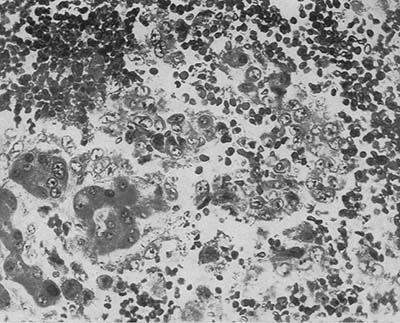

図7. 血液細胞に混じって腫瘍細胞巣が認められる.

図8. 大きなトロトラスト沈着巣

【要旨】70歳⼥性.58歳時に肝の梅毒⾁芽腫(ゴム腫)の診断に際してトロトラストによる動脈造影が⾏なわれた既往があり,その12年後に出⾎性ショックで⼊院,死亡した.

病理所⾒で,肝内転移を伴う出血性の肝腫瘍が認められると同時に,肝内にトロトラスト沈着巣が多発していた(図7,図8).脾,リンパ節,骨髄にもトロトラスト沈着巣が認められた.最終診断は,「多発転移を伴う肝内皮細胞肉腫からの致死的腹腔内出血.肝,脾,リンパ節,骨髄,骨,副腎,腎,血管壁の変性を伴うトロトラスト沈着と放射線障害」 であった.

肝内の最も大きなトロトラスト沈着部位に接して腫瘍が認められた.ホルマリンに12ヵ月水浸した肝ブロック標本をガイガーカウンターで計測すると,トロトラスト沈着部位で最も放射能が強かった.ラジウムによる骨肉腫誘発の臨床例,動物実験例が報告されており,二酸化トリウムによる腹膜肉腫,皮下肉腫の動物実験例もあることから,トロトラストによって肝肉腫が発生したと考えられる.

【解説】トロトラストによる動脈造影の12年後に,肝⾁腫が発生し,その腫瘍内出⾎が原因と考えられた症例報告で,トロトラストと腫瘍の関係については推測の域を出ないが,組織所見および過去の報告を強力な状況証拠として論じ,その因果関係をほぼ断定したという点で画期的な論文である.ただし放射線障害の機序としてはγ線が最も有害であるとしているが,実際にはα線の影響が主である.前掲のBlühbaumの論文でトロトラストが紹介されてから約20年を経ており,これ以前にもトロトラストの腫瘍誘発性については議論されてきたが,潜伏期が長いためにその認識にこれだけの時間がかかり,その間に多くの犠牲者が生まれた.